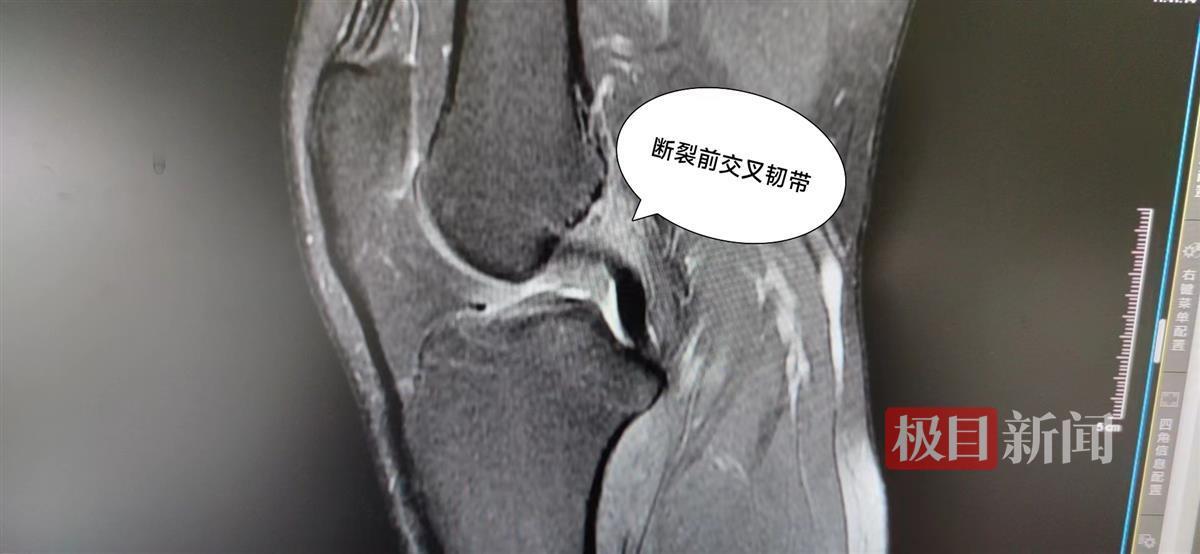

章先生的腿部影像检查报告(图片来源:武汉市第四医院)

在该院运动医学科,医生对其进行了详细检查。科室的张绍华医生介绍说,章先生这一次伤得不轻:不仅前交叉韧带出现了断裂,膝关节后外侧复合体,也就是外侧副韧带和腘肌腱部位也有损伤。经过评估,医生认为其手术指征十分明确,随后为其进行了交叉韧带重建手术,并修复了受损的复合体。手术进行得很成功,目前章先生已顺利出院,待恢复后可重新投入到运动中。